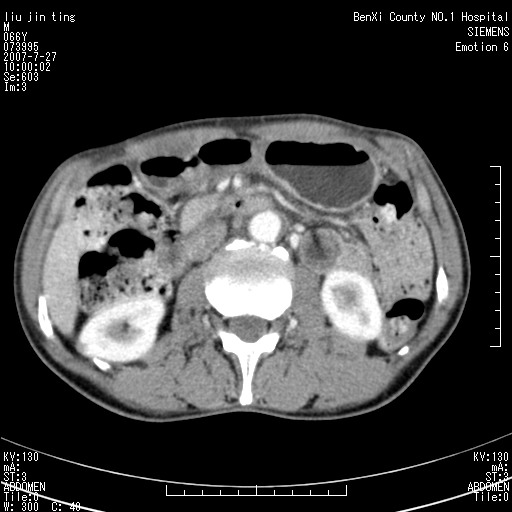

腹痛,背痛,无恶心呕吐,不黄,彩超示胰腺钩癌,ct扫描病灶平扫30-40hu,增强后动脉期40--60hu,静脉期50-68hu,真的是钩突上的么?您要试一试么?

动脉期

静脉期

沿着肠系膜上动脉呈匍匐性生长的软组织肿块,形态不规则,包绕肠系膜上动脉,呈明显强化,考虑来源于肠系膜的恶性肿瘤

沿着肠系膜上动脉呈匍匐性生长的软组织肿块,形态不规则,包绕肠系膜上动脉,呈轻-中度强化,考虑来源于肠系膜的恶性肿瘤。

钩突是正常的,只见腹膜后淋巴结的肿大,考虑淋巴瘤或转移可能。

支持!恶性纤维组织细胞瘤可能,与淋巴瘤及淋巴结转移鉴别(腹主动脉周围清晰,其他部位亦未见明显肿大淋巴结)。